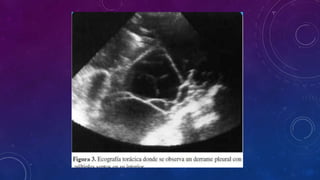

DIAGNOSTICO

ENVIAR EL LIQUIDO PARA ANALISIS

FISICOQUIMICO, CITOLOGICO Y

BACTERIOLOGICO.

TORACOCENTESIS O PUNCIÓN PLEURAL